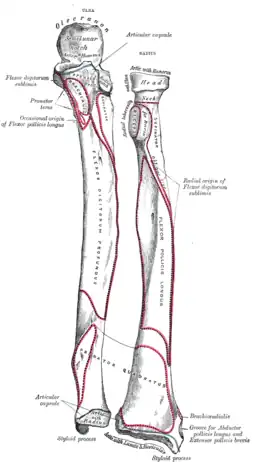

Insertion humérale du muscle supinateur (supinator) Insertions ulnaire et radiale du muscle supinateur (supinator)

Insertions ulnaire et radiale du muscle supinateur (supinator) Insertions radiale du muscle supinateur (supinator)

Insertions radiale du muscle supinateur (supinator)